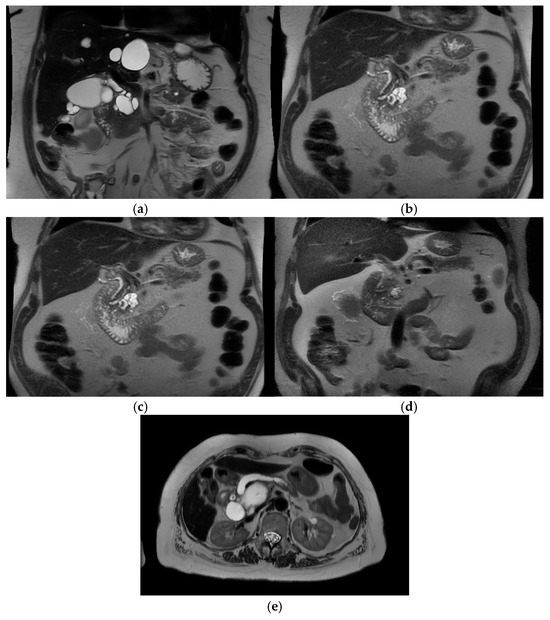

Intra-ductal papillary mucinous neoplasm (IPMN) is a benign condition that has an evolving area of management in the realm of pancreatic surgery. IPMN can be an incidental finding on radiological examinations with CT of the upper abdomen, and may have management with initial surveillance before patients are considered for surgery. See Figure 3a–e.

Figure 3. Branch duct IPMN and main duct IPMN. (a) Branch duct IPMN. Maximum size 3.2 cm. No other high risk or worrisome features. Incidental liver cysts. Resected—final histology IPMN with low-grade dysplasia. (T2-weighted MRI). (b) Branch duct IPMN >3 cm with thickened septations and nodularity—worrisome features. T2 Weighted MRI. Resected – final histology invasive cancer T3N2. (c) Same patient 1 year prior—approx. 3 cm size, “slightly thickened” septations. (d) Same patient 3 years prior. Smaller cystic lesion. No enhancing component. (e) Main duct IPMN—T2 weighted MRI showing grossly dilated main pancreatic duct.